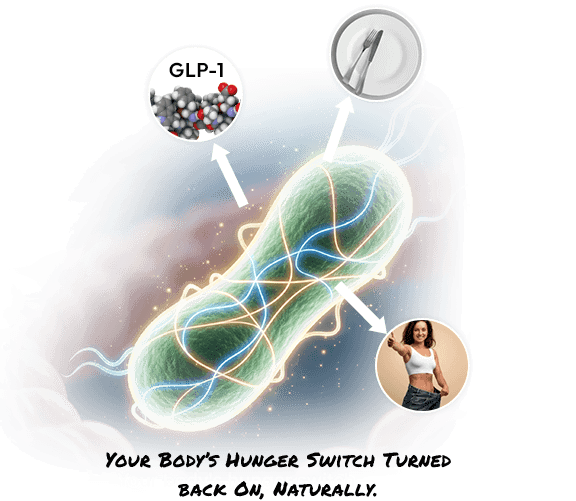

The Natural Alternative to Expensive Weight Loss Drugs

And then came the next-level find.

A bacteria called Akkermansia muciniphila.

Right now, weight loss drugs like Ozempic are the dominating headlines for their ability to help people lose weight.

But it comes with serious downsides…

- Injections

- Nausea

- Digestive Issues

- A Hefty Price Tag

Akkermansia offered something different.

It worked upstream of the popular injection.

Not by mimicking hormones...

But by helping your body naturally produce more of them.

Specifically, it increased that hormone ... the same hunger-regulating hormone that drugs like the popular injection target.

But without the side effects.

And without synthetic interference.

One human study showed that people taking Akkermansia lost over 5 pounds in just a few weeks.

Without changing anything else.

And when combined with the RS2 and butyrate boosting Chickory Root...

The effects weren't just additive...

They were exponential.